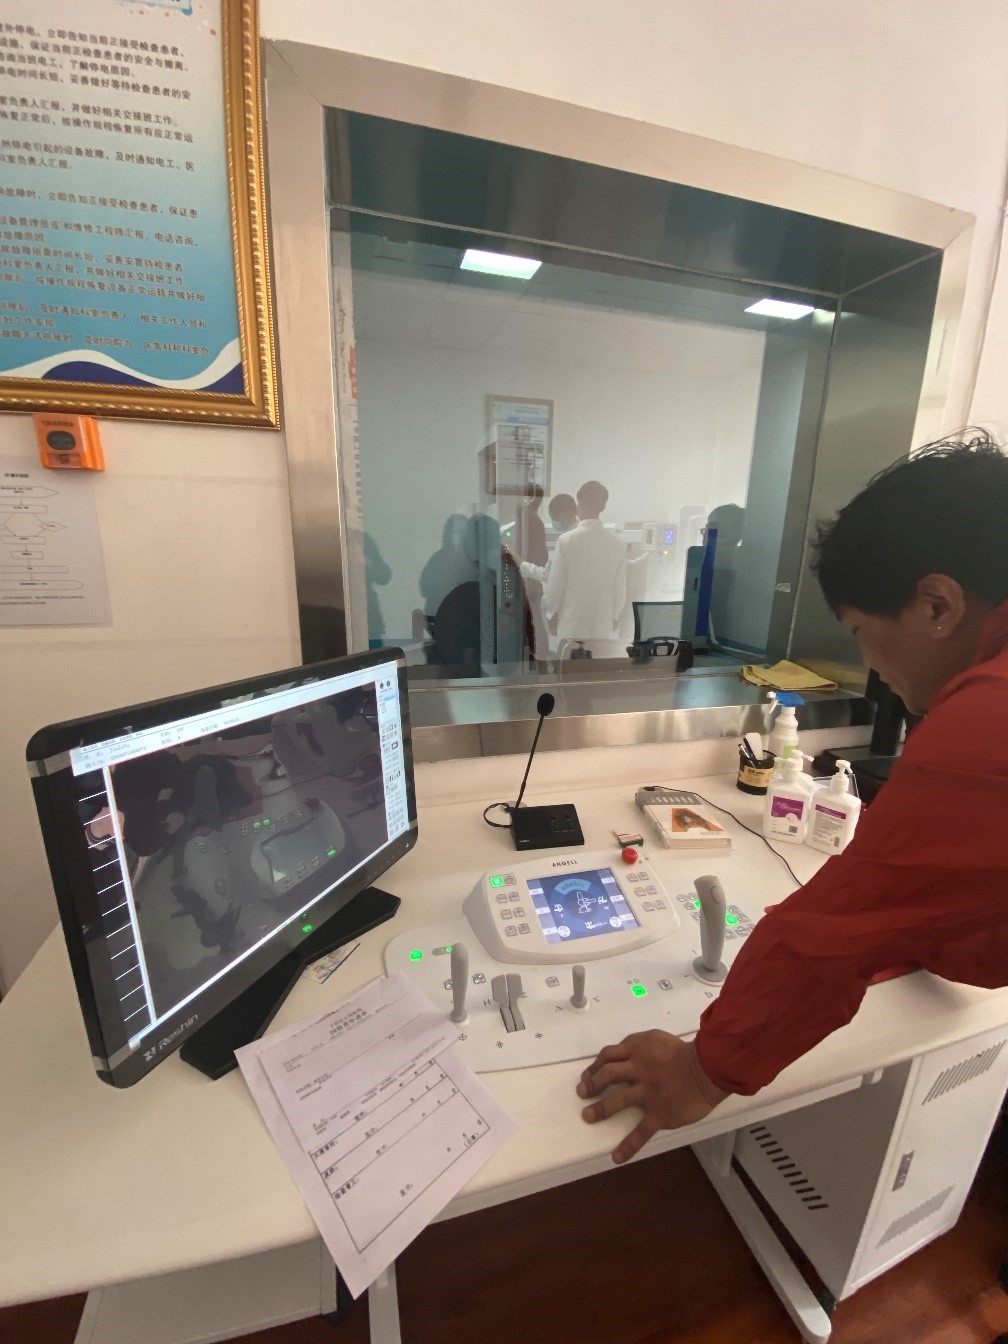

“这个设备好得很,现在我们这个医院就1台这个设备,每天都在给病人做检查。摁一下摁扭它就可以立起来,体检病人的时候我们就立起来检查,拍出来的图像很清楚。它也可以横着放,拍腰椎的病人、骨关节的病人,我们摁一下就可以平放摄片。我们现在已经检查了差不多有1多万个病人了,机器没有出现什么问题,工程师也会经常询问设备的情况,这个设备美得很。”操作设备的主管技师说。

目前,卡若区人民医院放射科仅有3名技术与诊断医师,都是昌都本地的藏族年轻人,没有像内地城市的二甲医院放射科进行技术与诊断的分组,在卡若技师也是诊断医师。技师每天既要完成摆位、摄片,同时也要完成阅片与诊断报告的书写,承受着艰巨的检查任务与诊断压力,确保让每一位患者都能得到精准的检查保障。这种情况,在藏区也是普遍的现象,缺少医师是目前藏区医疗服务能力建设中比较急迫的问题。

图5:技师为藏民百姓进行摄片检查